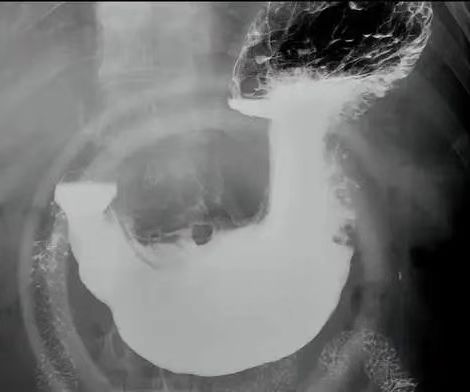

消化道造影全称为X 线气钡双重对比造影,核心原理是利用钡剂(高密度)与空气(低密度)的对比,通过 X 线摄片呈现消化道壁的形态、轮廓及功能状态。检查时患者需口服钡剂(有时需加服产气粉),在不同体位下,医生通过 X 线机捕捉食管、胃、十二指肠及结肠的充盈、黏膜和排空影像,判断是否存在溃疡、肿瘤、狭窄等结构异常。

消化道造影对食管憩室(检出率 0.73% vs 胃镜 0.15%)、管壁僵硬等结构改变的识别更具优势。